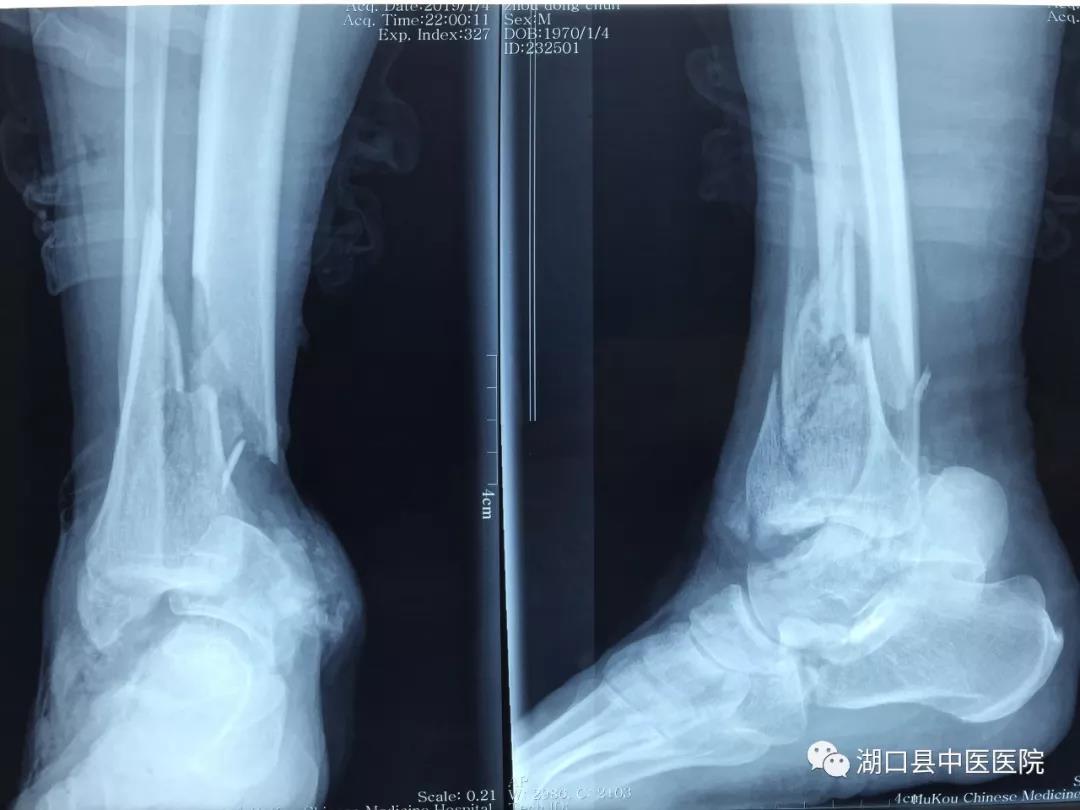

时间回到今年1月4日。晚间10时左右,刚做了2台急诊手术正准备休息的吴学峰医师接到急诊电话,有一名严重车祸伤患者,右下肢伤势严重,请求会诊。吴医生放下电话,急忙赶到急诊科。现场一看,患者周大叔伤情非常严重,右小腿被碾压得血肉模糊,受伤部位骨头外露,面色苍白,烦躁不安。血压80/50mmHg,肢体远端冰凉干瘪,摸不到血管搏动。病情之棘手超乎想象:一是伤者右下肢系车轮重物碾压后不全离断,皮肤软组织损毁严重、部分缺失,胫骨中下段、距骨、跟骨粉碎性骨折伴踝关节脱位;二是血管神经肌腱碾压离断,血管缺损;三是伤处沾满泥沙,污染严重。面对这些不利情况,通常来说进行截肢手术是最为稳妥的办法:手术难度低、过程短、风险小、费用低、后期并发症少。

按照预定计划,手术有条不紊地进行着,骨折的外固定支架临时固定,在显微镜下进行血管、神经的逐一吻合,肌腱的修复……经过6个多小时的持续作战,次日凌晨5时许,周大叔离断的下肢逐渐恢复红润,断肢再植术完成,手术成功。在骨伤科医护团队的密切配合和不懈努力下,经过抗凝、解痉、抗感染等治疗措施,右小腿血运良好,一期肢体成活。在周大叔住院期间,骨科专家柯阳春院长始终惦念着他的病情,经常来到病房看望了解情况。二期周大叔由于外伤导致踝关节周围皮肤缺损,胫骨及肌腱外露同时伴有感染,传统的植皮方法无法解决问题。骨伤科团队在柯院长主持下经过讨论后,决定应用显微外科技术吻合血管的游离股前外侧皮瓣修复创面,周大叔得以顺利康复出院。经了解,此例游离皮瓣修复创面为湖口县首例。